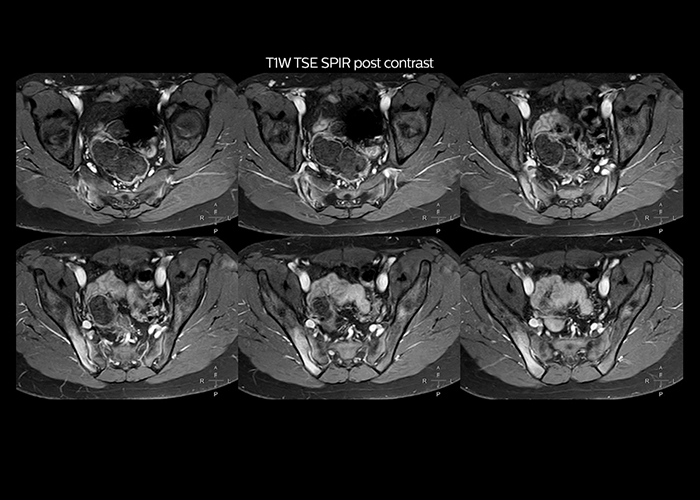

“On average, we scan about 80 patients per day, but on some days we scan well over 100 patients. The scanner is in use 7 days per week, operated 20 hours per day on week days and 8 hours per day in the weekend,” Mr. Tuna says. “To avoid coil changes we plan examinations of similar anatomies back to back, such as head and spine. Multiva helps us here a lot because coils don’t need to be changed frequently. Moreover, thanks to parallel imaging technology and 16-channel HeadSpineTorso and 8-channel MSK coils we are able to achieve excellent image quality. In this way Multiva helped us to increase both image quality and productivity.” “Neurological cases, such as brain and spine imaging, represent the largest share in our MR scanning, followed by musculoskeletal cases. In general, we use simple and basic imaging protocols. But occasionally, we use advanced techniques for problematic cases if necessary.

“Since we have Multiva, we have improved our workflow, because it has been so easy for our operators to learn and use Multiva. Our operators notice that the coils are lightweight and coils don’t need to be changed frequently. The user interface is easy to use. Features like this help us to scan a high number of patients. For instance, the musculoskeletal coils can be used interchangeably, and due to the user-friendly interface, the number of mistakes such as, for example, correct coil element selection has decreased significantly, because the system does it automatically by itself.” “Most important, Multiva satisfies our clinical imaging needs very well,” says Mr. Tuna. “Many features of Multiva have become similar to the Ingenia system. Even in more complex imaging such as abdominal and cardiac, the image quality and performance of Multiva is better than we expected. General surgeons and physicians from our hospital’s internal medicine department prefer to refer to us because of this.”